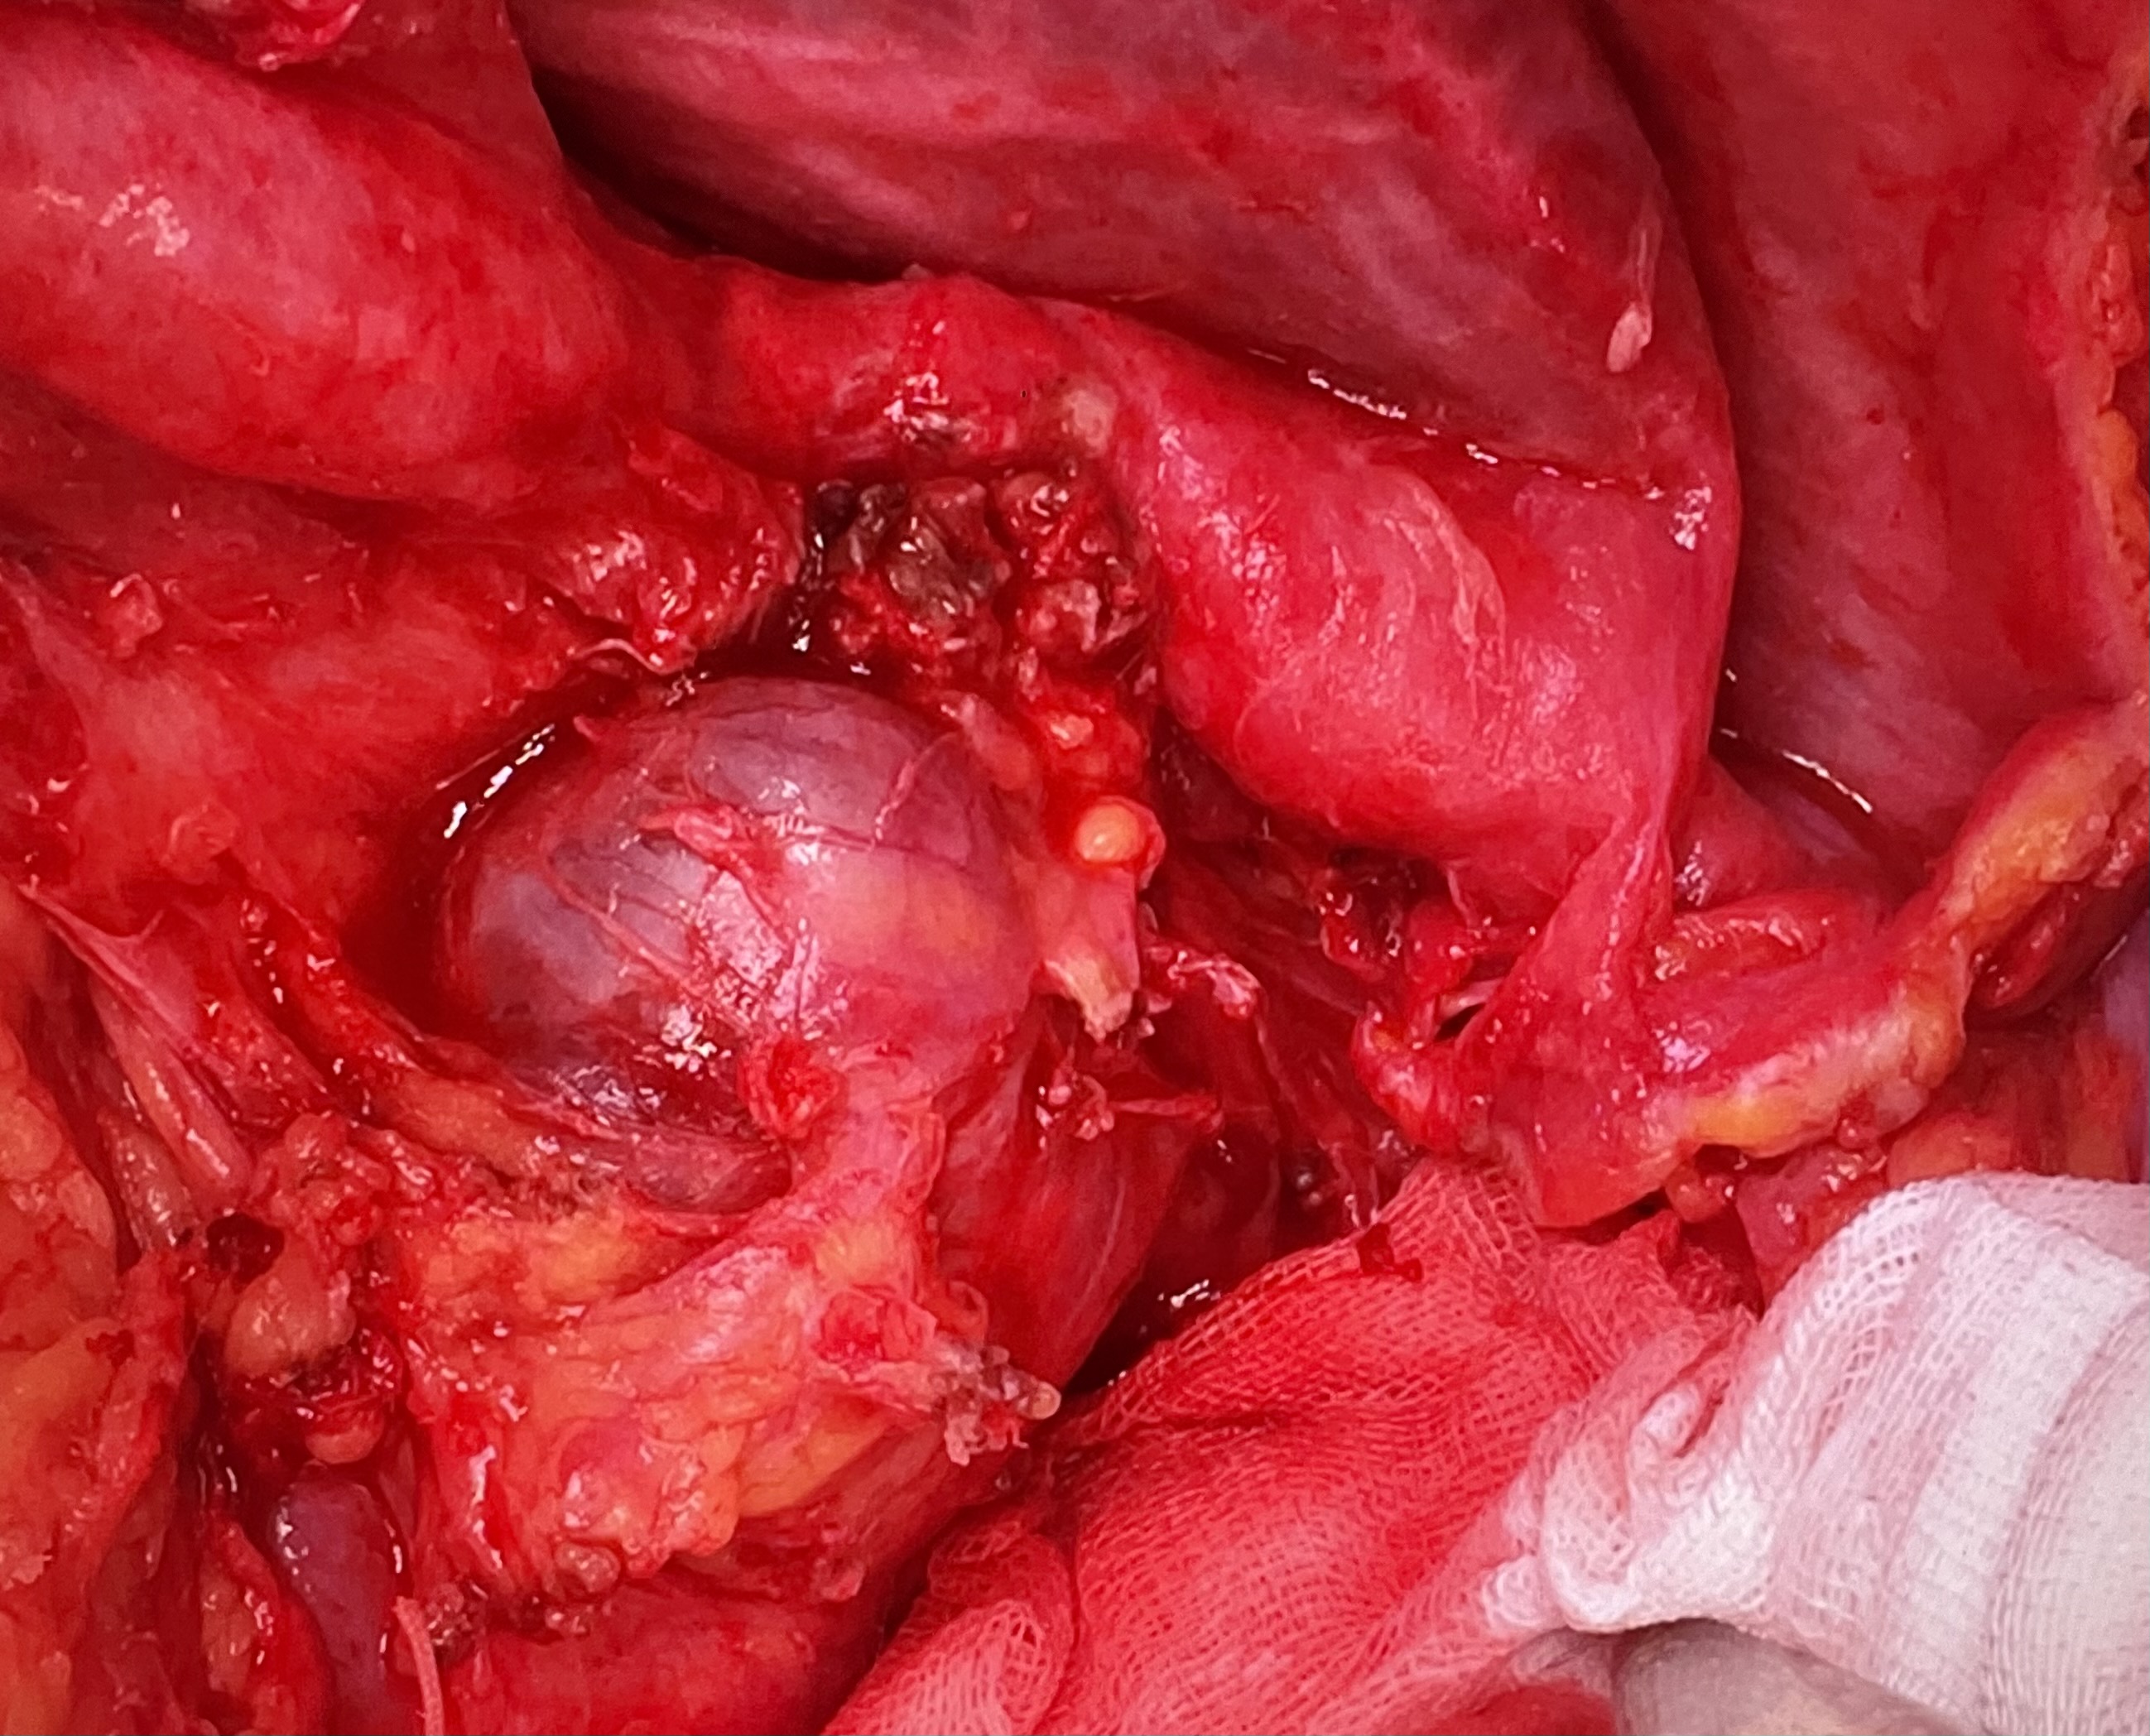

6. Выделение поджелудочной железы с конгломератом, образованным кистой, артерии-венозным соустьем и аневризмой селезеночной вены. Перевязка селезеночной артерии дистальнее окклюдера | |

7. Ложе удаленного конгломерата и дистального отдела поджелудочной железы. Обнаружение гипертрофированной добавочной селезенки. | |